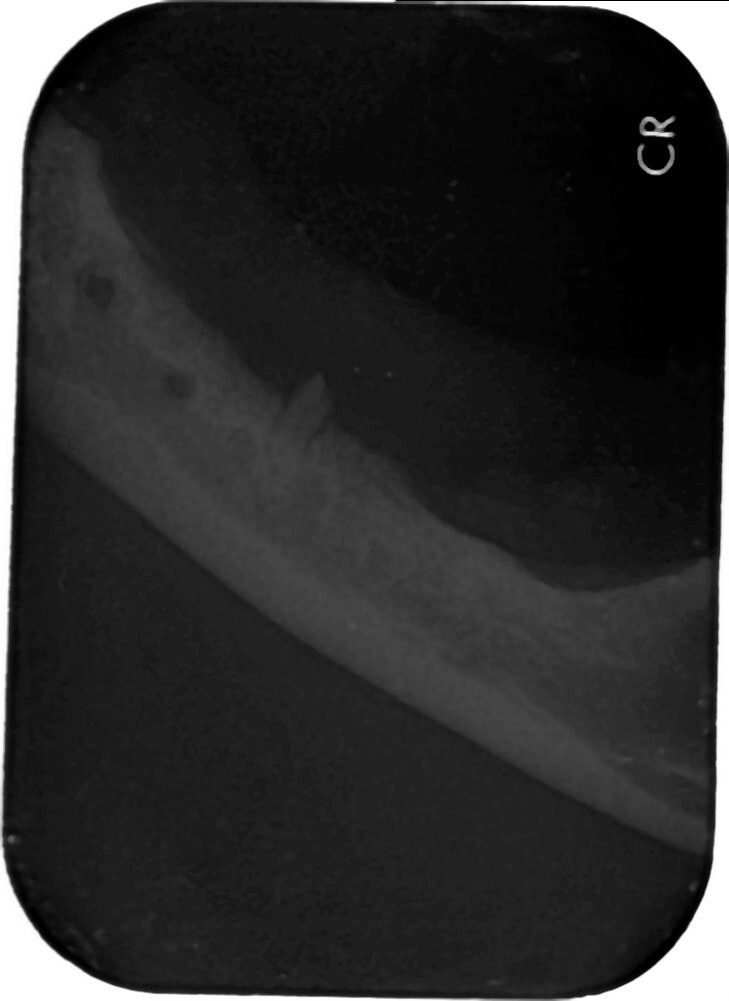

於他家醫院建議拍攝齒科x光 懷疑齒根殘存

10/5門診時 口內檢查可摸到雙側下顎有殘存齒根

10/18維康麻醉進行齒科x光

及殘存齒根拔除

只發現下顎雙側各一齒根(如同門診可觸摸處)

本筆醫藥費用即為盈盈於維康進行齒科X光及殘存齒根拔除的費用